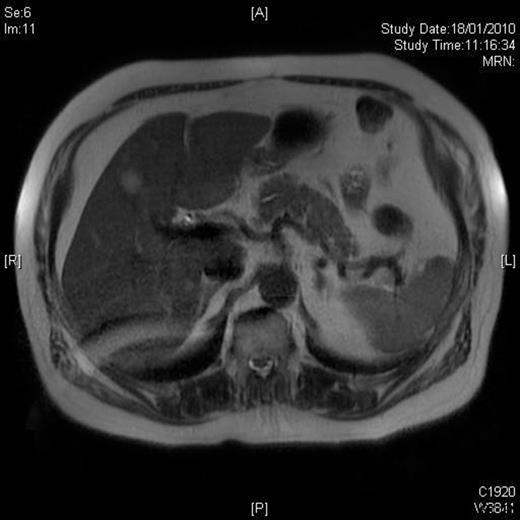

A 58-year-old Caucasian man presented with chest pain, on a background of type-II diabetes mellitus, hypertension and hypercholesterolaemia. A Cardiologist excluded ischaemic heart disease. Full blood count was normal, and an ultrasound scan of the abdomen revealed a 5.5-cm splenic lesion. Computed tomography (CT) revealed a 55mm X 36mm hypodense lesion in the upper pole of the spleen, while magnetic resonance imaging (MRI) demonstrated a well-circumscribed exophytic round mass arising from the anterior aspect of the spleen with features compatible with a benign solid tumour of uncertain malignant potential and multiple liver haemangiomas [Figures 1 and 2]. We proceeded to LPS after the patient had received preoperative vaccinations lest total splenectomy might be necessary.

T2W weighted image demonstrating a well circumscribed, round mass arising exophytically from the anterior aspect of the spleen with an intermediate T2W signal intensity.